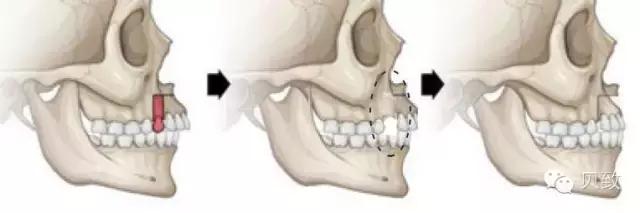

矫正时牙齿之所以能在口腔中移动,主要是因为包裹牙根的牙槽骨具有终生改建的能力。牙槽骨的重建作用,有点类似于“拆东墙补西墙”。

当牙齿向前移动,持续的压力作用到牙槽骨上时,受力部分的牙槽骨会逐渐被吸收,给牙齿的移动开辟了空间。而包绕在牙齿后侧的韧带会受到牵拉,提示它需要修复因牙齿移动所产生的缝隙啦,机体立即会长出新的牙槽骨来填补多出来的空隙!这么一吸一补,牙齿就能在牙槽骨中稳稳地移动啦~

在改建周期完成以后,这颗牙齿依然被牙槽骨紧密包围,不留空隙,但位置已经产生变化了,完美解决牙列缺损、拥挤问题,何来牙齿倾斜松动一说?